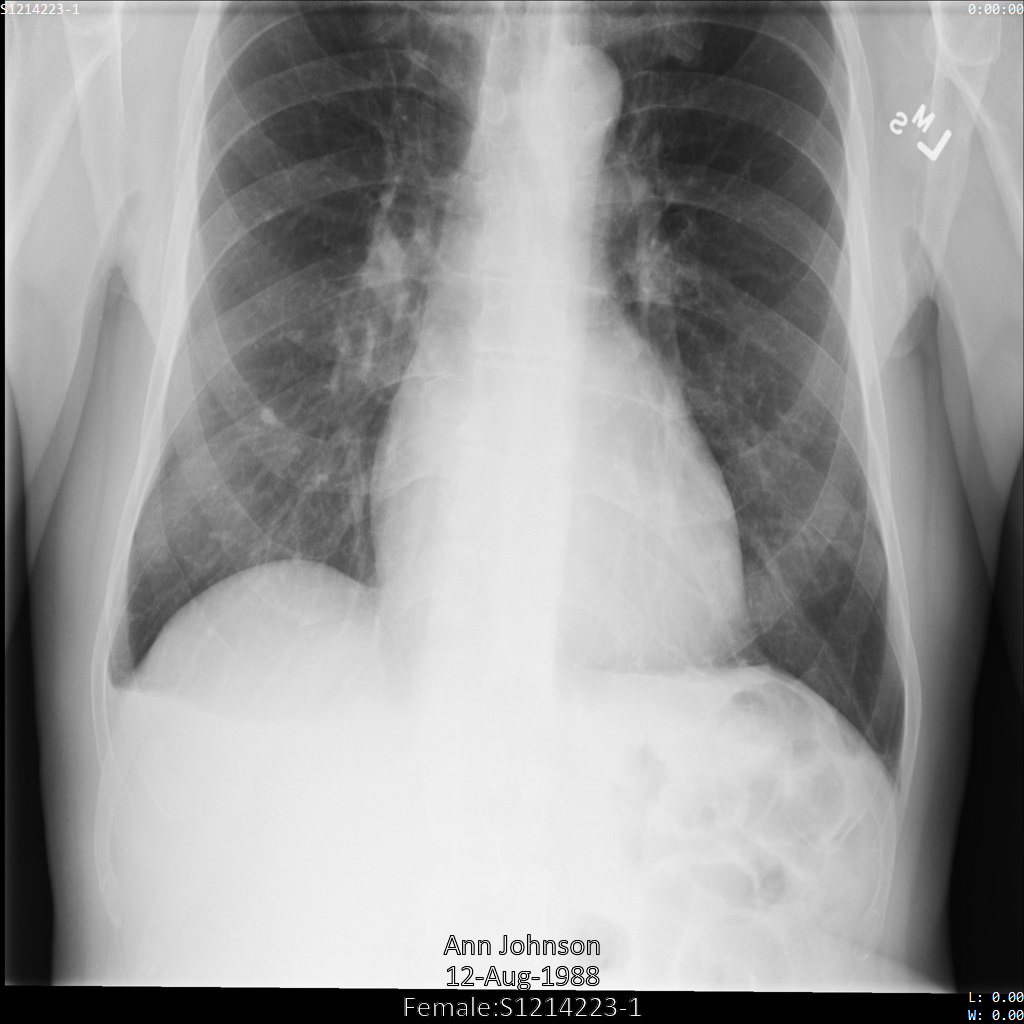

Después de enviar la imagen a la API Cloud Healthcare, la imagen aparece de la siguiente manera. De las etiquetas proporcionadas en removelist, solo se elimina PatientBirthDate

de la imagen, ya que es la única etiqueta de removelist que

corresponde a metadatos visibles en la imagen.

Aunque el PatientBirthDate de la esquina superior de la imagen se ha ocultado de acuerdo con la configuración de la lista de elementos que se deben eliminar, la información sanitaria personal (ISP) grabada en la parte inferior de la imagen permanece. Para quitar el texto insertado, consulta Ocultar el texto insertado de las imágenes.